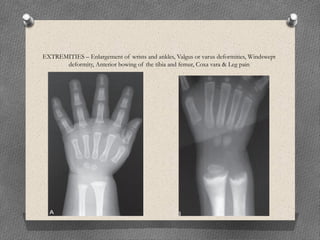

EXTREMITIES – Enlargement of wrists and ankles, Valgus or varus deformities, Windswept

deformity, Anterior bowing of the tibia and femur, Coxa vara & Leg pain